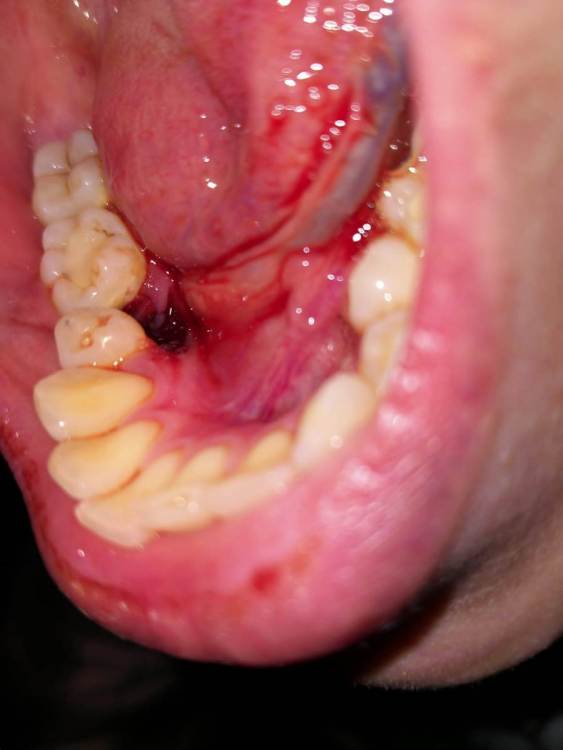

Здравствуйте.Удалили зуб в субботу, сегодня  вторник .Удаление было сложное.Сейчас из симптомов:постоянная пульсирующая боль,боль в ухе , опухшая щека,небольшое увеличение лимфоузлов. Была у врача который делал удаление в понедельник вечером.Посмотрел сказал , хотел залезть во внутрь,решил посоветоваться с другим врачом.и по совету другого врача не стал трогать. Оба молодых парня, почему то не очень вериться  , что это норма

3 и 5 фото как выглядит все сейч2B56CE66-56D0-4E1D-86A5-4E21849A5812.thumb.jpeg.abaa6f2b73e64da65817873712d3f05f.jpegE0B4CA80-B424-481A-84A3-CF3E12CB7724.thumb.jpeg.6413038171f373f539cc920d011ca1ae.jpegC7227F50-6100-4A26-A12F-E31C37F9D8B0.thumb.png.940d35b1a889de5ed43a9a7bb34ec48f.png1C299E13-97B5-4B9F-97A7-C54C58DB2369.thumb.png.14be377876310f3f10fa0a57b31c5ea7.png743AD060-C0D2-4F96-9EFE-2BF3908D1153.thumb.jpeg.593d27327ab5e07b3e1f53754b9b9614.jpegас

Антисептические ванночки,аппликации с гелем "Метрогил-Дента" на лунку. Пока там есть сгусток ,если же сгусток разрушится ,надо будет вымывать еду шприцем с обломанной иглой из лунки и вводить туда тот-же гель "Метрогил-Дента" Я не пойму по снимку - там участок кости оголён у Вас с язычной стороны или там всё мягкое?